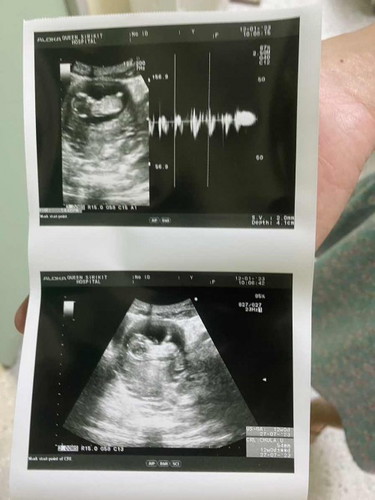

13 วีค น้องตัวเล็กไปมั้ยคะ

ถามหมอว่าน้องโตช้าไปมั้ย หมอบอกไม่ช้า ปกติดี แต่ในภาพคือดูไม่ค่อยออก ว่าน้องนอนหันหลังหรือเปล่า

ของเรา12w 6.58 แต่หมอบอกว่าปกติค่ะ ถ้าคุณหมอบอกว่าตามเกณฑ์ไม่น่ามีอะไรน่าเป็นห่วงนะคะ

เชื่อหมอค่ะแม่ อยากรู้ขนาดเทียบกับในแอปดูค่ะ 5.4 ซม ก็ไม่เล็กนะคะปกติ

13w น้องยังเล็กมากค่ะ ของเราซาวด์ตอน13w 6.6 เซน😊

ไม่เล็กนะคะ13w5.4เซน เราซาวด์ตอน 11 w4.7เองคะ

เพิ่ง 13wเองน้องก็ตัวนิดเดียวจริงๆค่ะ